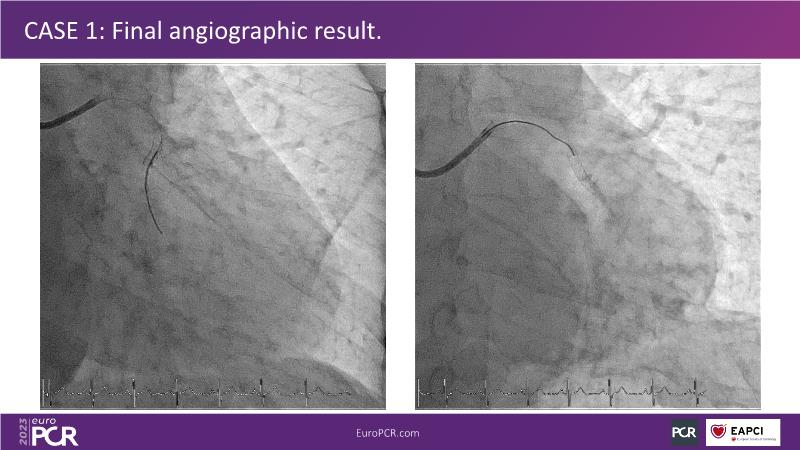

• To understand why you can count on customised drug delivery platform of DES+DCB in complex settings with imaging-based evidence through case presentations

• To gain an insight on how the next generation no-polymer DES+DCB stent platform will address the unmet needs in coronary artery disease patients